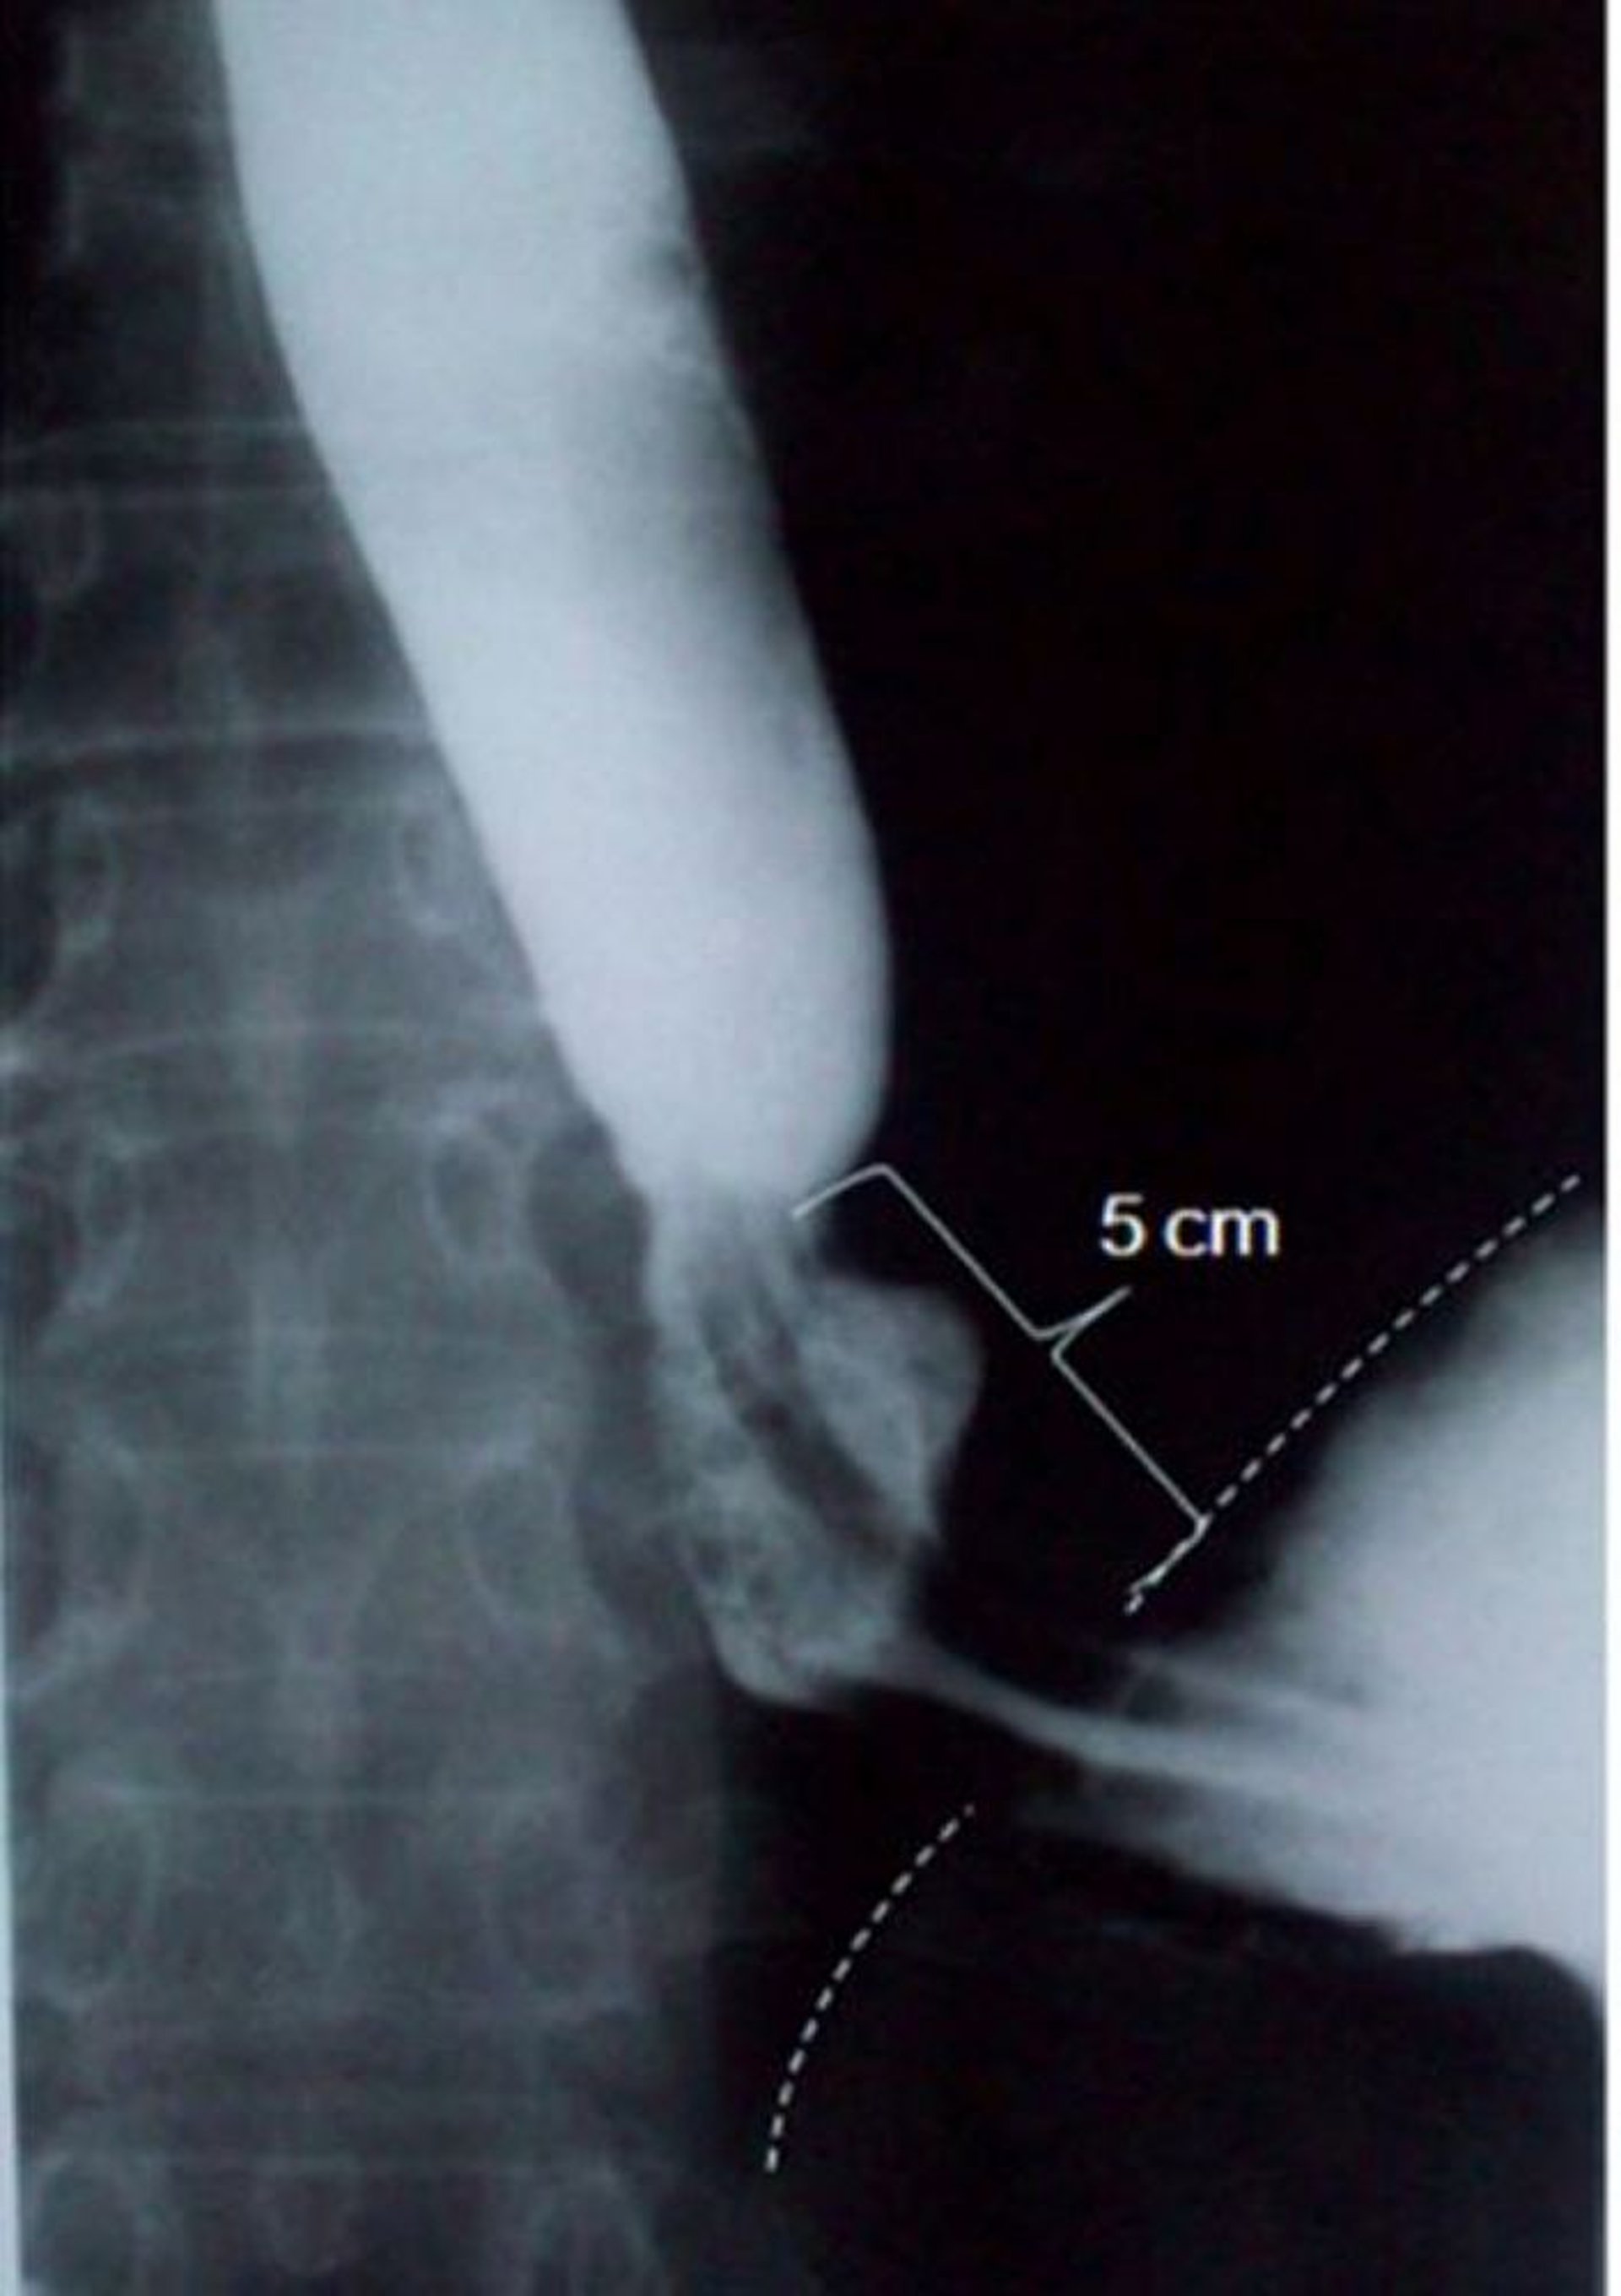

Pasto baritato che mostra ernia iatale da scivolamento

Questa immagine mostra un'ernia iatale da scivolamento di 5 cm di lunghezza assiale (una linea tratteggiata indica il bordo diaframmatico).